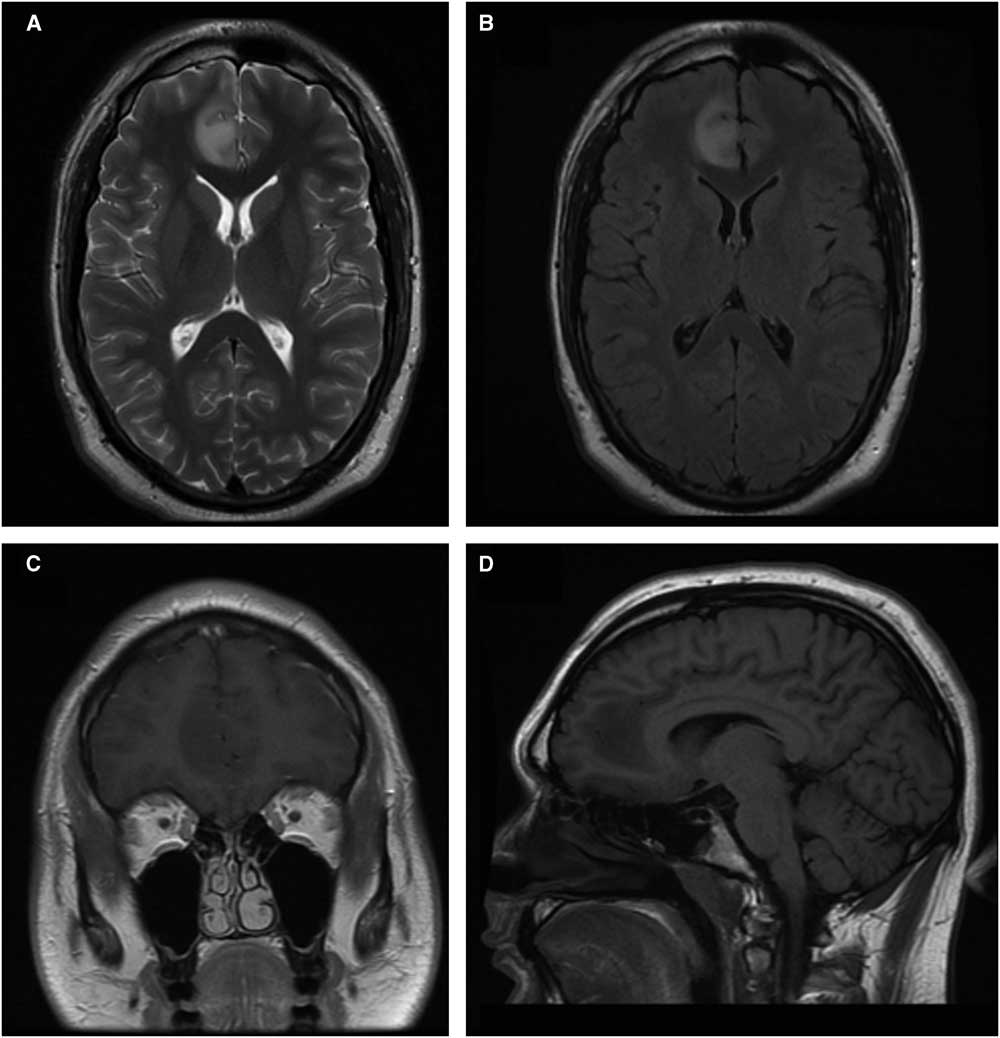

A 20-year-old male with suspected arteriovenous malformation of the right pinna underwent MRI. None was found; however, the gadolinium-enhanced MRI showed an incidental solitary lesion (32×30×17 mm) in the medial right frontal lobe (Figure 1), involving the parasagittal cortical ribbon and subcortical white matter. The area was hypo-intense on T1-weighted imaging and hyper-intense on T2, with no diffusion abnormality or enhancement. There was no midline shift, hydrocephalus, or abnormal flow void(s). The patient had no neurological or systemic symptoms. Past medical, family, and social history were unremarkable.

Figure 1 MRI images of focal cortical dysplasia associated with oligodendroglioma. Axial (A) and axial fluid-atenuated-inversion-recovery (B) T2-weighted images. Coronal gadolinium enhanced (C) and sagittal (D) T1-weight imaging.